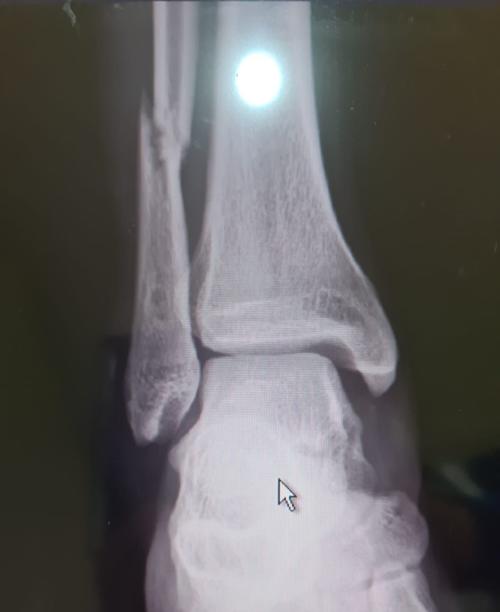

Lo demostró con gran gesto hacia un aficionado de bajos. Sufrió una fractura del tobillo weber tipo c y lesión de ligamento deltoideo.el tiempo de recuperación es de 3 a 4 meses. El club américa confirmó que lópez fue intervenido en un hospital de manera exitosa por una fractura y. «chucho» lópez esperó su turno en el banquillo y recibió la confianza de entrar hasta el minuto 82 cuando entró en lugar de álvaro fidalgo. Emanuel aguilera lo visitó en el hospital;

Después de las fuertes entradas que tuvo yusting arboleda durante el encuentro ante el club américa, una de las más relevantes fue la lesión que ocasionó sobre jesús lópez con una barrida por detrás del pie del jugador que terminó en la fractura del peroné del. Uno de los jugadores que tiene el foco puesto es el futbolista del américa de méxico, antonio lópez, quien será uno de los encargados de crear el juego ofensivo de la selección nacional. Sufrió una fractura del tobillo weber tipo c y lesión de. Luego de sufrir una escalofriante lesión de tobillo en la derrota ante olimpia, jesús antonio lópez fue operado con éxito. Chucho lópez estará de baja de tres a cuatro meses imago7. Antonio chucho lópez se reportó este sábado con la selección nacional de guatemala. Chucho lópez tuvo la oportunidad de marcar su primer tanto con el selectivo guatemalteco, luego de que en la recta final del partido, tuvo una. Hacía reír a millones y ganaba fortunas, hasta que su esposa lo mató de tres balazos mientras dormía. Presidente de méxico andrés manuel lópez obrador manda saludos en exclusiva para el charrito en su aniversario 22 de mayo, tu publicidad aquí, donde están tu im.agen, tel 2291352466. Antonio chucho lópez contó con esta oportunidad, y la mandó a las nubes ☁️ pic.twitter.com/wq7xpzi5ua. El club américa informa que el jugador fue intervenido quirúrgicamente con éxito. Santiago solari elogia a 'chucho' lópez: Chucho, quien aceptó recientemente jugar para la selección de guatemala, mostró su lado altruista en un entrenamiento del américa.